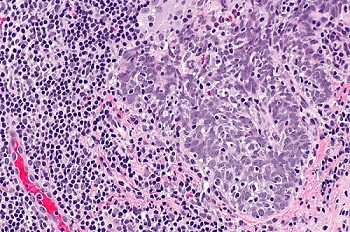

应用类似原理,还有不使用荧光染色的免疫组化(IHC)染色,主要用于尸检研究,判断病毒对身体各器官的感染情况,比如新冠病毒和猴痘病毒都能找到相关研究。

IHC免疫组化染色,猴痘病毒感染犬的支气管(红色为病毒反应)